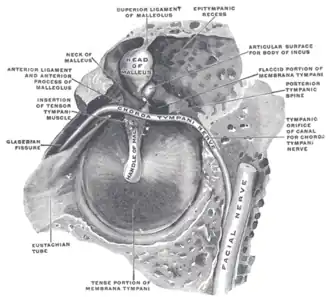

Middle ear, with auditory tube at bottom right | |

View of the inner wall of the tympanum (enlarged)

View of the inner wall of the tympanum (enlarged) -

The right membrana tympani with the hammer and the chorda tympani, viewed from within, from behind, and from above

The right membrana tympani with the hammer and the chorda tympani, viewed from within, from behind, and from above